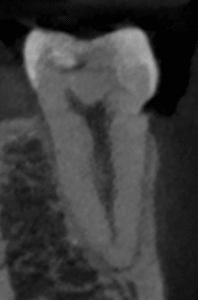

チャンバーオープンした。

やはり血まみれだ。

以下のように根管形成した。